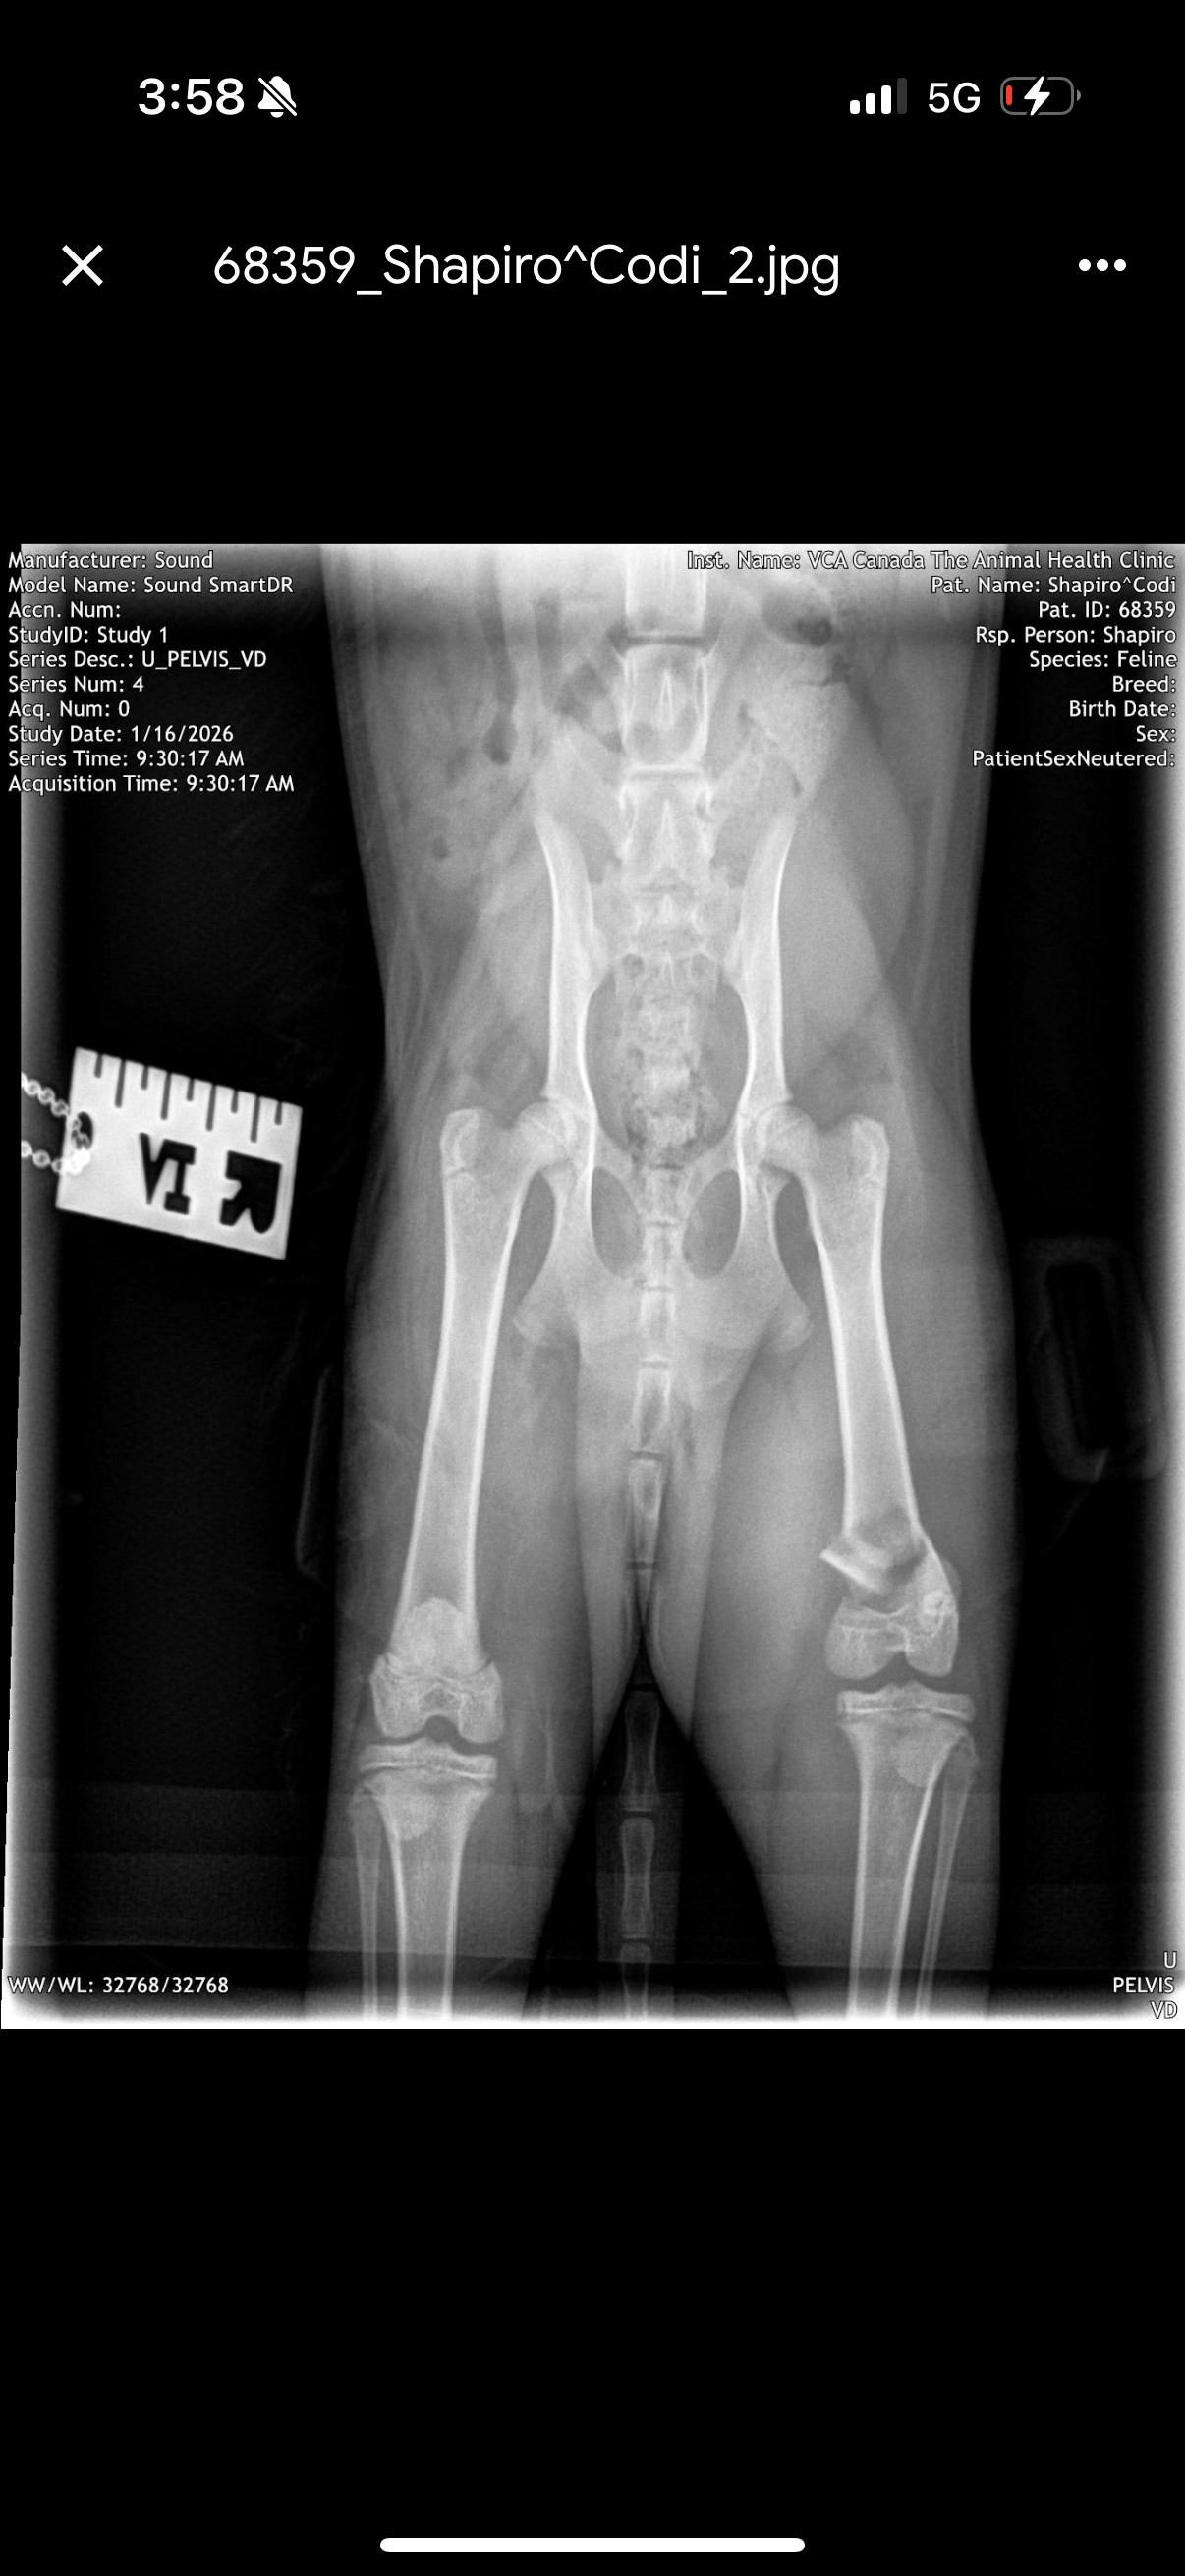

This is Codi, my 4.5–5-month-old kitten. She’s sweet, playful, and still just a baby. A sudden accident left her with a severe fracture to her left back leg, and she’s in pain but can absolutely recover with treatment.

Because I don’t have pet insurance, the emergency vet quoted up to $7,500 + tax for orthopedic surgery — a cost I simply cannot afford. I live in Montreal and am actively pursuing lower-cost options, and discussing hind-leg amputation as a last resort, which is a humane and successful option for many cats. Even these options still cost thousands of dollars, and time is critical.